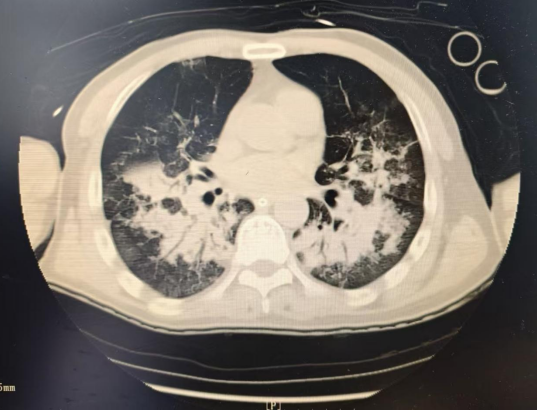

严密监护、及时调整治疗策略、控制感染、肠内营养、气道管理、皮肤管理、心理护理、预防并发症……经过全科医护人员的不懈努力,20多天惊险紧张的救治后,从“鬼门关”走了一圈的老吴终于化险为夷,感染得到有效控制,多器官衰竭逐步逆转,最终成功脱离呼吸机,顺利转入普通病房进行后续治疗。

治疗后CT影像